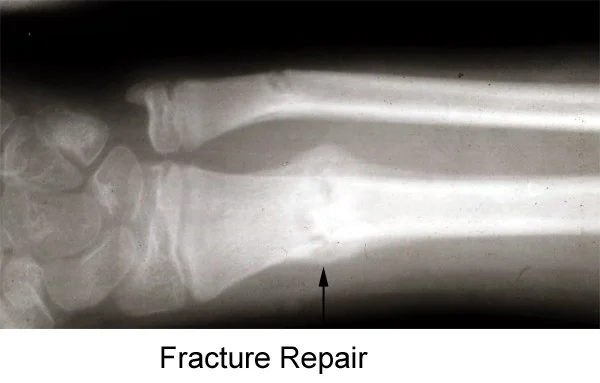

- Fractures are joined initially by a cuff of provisional woven bone (bridging external callus). This varies in amount. CC Y ⇒

- cortex - to - cortex union ⇒

- late medullary callus ⇒

- Remodelling and the gradual replacement of bridging bone by medullary callus